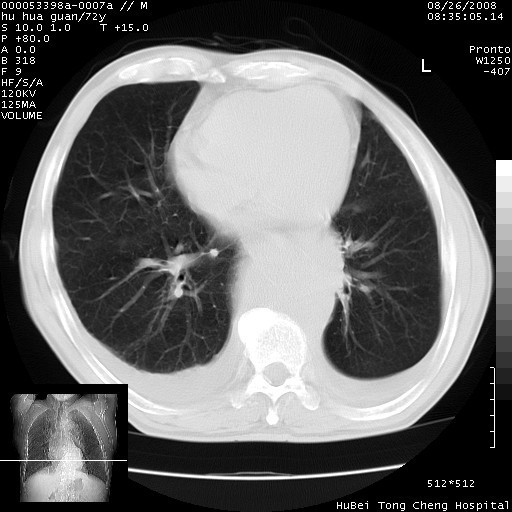

标题: CT15582:M,72Y。请老师帮分析胸部病变。

可以明确的说。肯定不是主动脉夹层破裂出血!考虑为淋巴瘤或间叶组织来源的恶性肿瘤可能性大。右肺小结节建议薄层观察,如能发现恶性征象,那椎前改变就考虑为转移所致。至于双侧少量胸水乃静脉血回流受阻所致。

1、右肺周围性肺癌、胸腔积液(双)

1、右上肺结节病变,肺泡癌不除外,请随诊;左下肺近后纵隔病变,考虑纵隔型肺癌侵犯大血管可能;

2、右下肺背段少许炎症,双侧胸腔积液,右下肺纤维索条。

降主动脉前移位,后纵隔占位

后纵隔占位,降主动脉前移位;双侧胸腔积液;应排外食管病变侵犯血管可能;